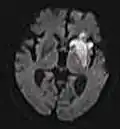

Sequências

Uma sequência de RM (Ressonância Magnética) é uma configuração particular de pulsos de radiofrequência e gradientes, resultando em uma imagem específica.[65] O ponderamento T1 e T2 também podem ser descritos como sequências de RM.

| Grupo | Sequência | Abreviatura | Física | Distinções clínicas principais | Exemplo |

|---|---|---|---|---|---|

| Ponderado em difusão (DWI) | Convencional | DWI | Medição do movimento browniano das moléculas de água. | Sinal alto dentro de minutos após um infarto cerebral.[77] |  |

| Coeficiente de difusão aparente | ADC | Ponderamento reduzido em T2, usando várias imagens convencionais de DWI com diferentes ponderações de DWI, sendo a mudança correspondente à difusão. | Sinal baixo minutos após um infarto cerebral.[78] |  | |